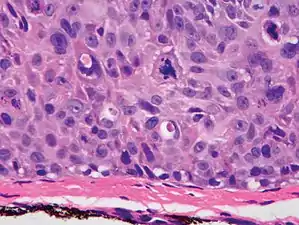

cSCC in situ, high magnification, demonstrating an intact basement membrane.[12]

Superficially invasive cutaneous squamous-cell carcinoma. These lesions often do not show the marked pleomorphism and atypical nuclei of cSCC in situ, but manifest early keratinocyte invasion of the dermis.[12]

High magnification demonstrates the pleomorphism of the invading keratinocytes[12]